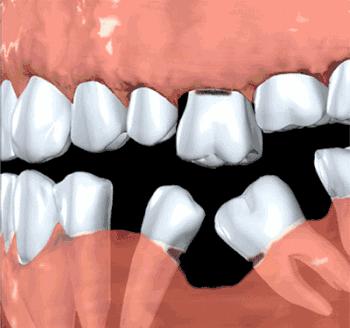

牙齿缺失长时间不进行修复,相邻以及对颌的牙齿就会失去“依靠”和对应的“约束”关系,那么,久而久之,这些牙齿就会倾斜,从而导致咬颌功能的紊乱。

缺牙长期不修复,在日常的使用中,两侧的牙齿失去原有的支撑压力,这时候牙齿倾斜,久而久之就会出现牙齿松动,最终变成牙齿脱落。